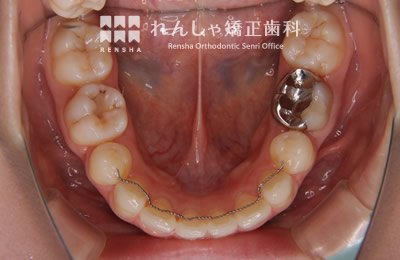

右下7番目(12歳臼歯)がなかなか出てこないため、6歳臼歯を支えに引っ張り出しました。

治療前

→

治療中

治療後

| 主訴 | 前歯のがたつき |

|---|---|

| 診断名 | Angle Class I 叢生 |

| 初診時年齢 | 10歳10か月 |

| 装置名 | 舌側弧線装置 |

| 抜歯非抜歯 | 非抜歯 |

| 治療期間 | 3年10か月 |

| 費用の目安 | 約36万円+消費税(検査料金、都度の処置費用等も合わせた総額) |

| リスク副作用 | 歯の移動に伴う軽微な歯根吸収、歯槽骨吸収、歯肉退縮(いずれも本症例ではほぼ無し)、矯正器具装着中のカリエスリスク増大(本症例ではカリエス発生無し) |